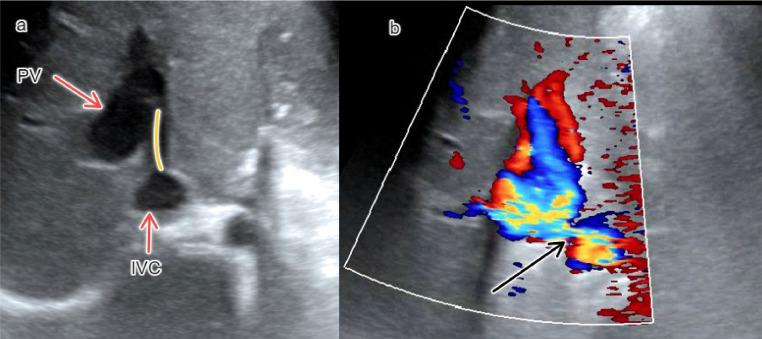

Congenital portosystemic shunt (CPS) is a rare vascular anomaly resulting in diversion of splanchnic or portal blood into the systemic circulation. Other vascular malformations associated with this entity are uncommon. A 4-year-old female child with a diagnosis of acute viral hepatitis had an incidental finding of extrahepatic CPS on a Doppler abdominal ultrasound. Contrast-enhanced computed tomography showed a dilated portal vein having H-type side-to-side communication with a hypoplastic intrahepatic portion of the inferior vena cava and a prominent dilated azygos vein. There was retroaortic left renal vein drained into the IVC which was visualized in its entirety. Echocardiography findings were normal and the patient was discharged after symptomatic treatment that achieved improvement. With the expansion of abdominal imaging, incidental cases of CPS are increasingly being diagnosed in children. Although vascular malformations associated with CPS are rare, early diagnosis of cases helps avoid complications during shunt closure.

先天性门体分流(CPS)是一种罕见的血管异常,导致内脏或门静脉血分流至体循环。与此相关的其他血管畸形并不常见。一名诊断为急性病毒性肝炎的4岁女童在腹部多普勒超声检查时意外发现肝外CPS。增强计算机断层扫描显示门静脉扩张,与发育不全的肝内下腔静脉部分呈H型侧侧连通,奇静脉显著扩张。主动脉后左肾静脉引流至下腔静脉,全程可见。超声心动图检查结果正常,患者经对症治疗后症状改善出院。随着腹部影像学检查的普及,儿童CPS的偶然病例诊断越来越多。虽然与CPS相关的血管畸形很少见,但早期诊断有助于避免分流闭合时的并发症。